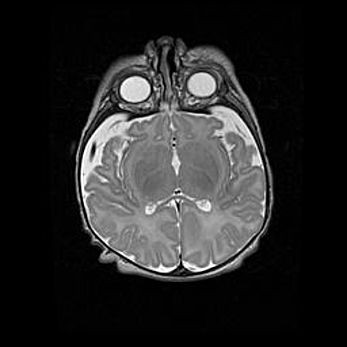

Неполная лизэнцефалия (пахигирия). Открытая гидроцефалия.

Возраст: 17 дней

Вес: 3110 г

Пол: мужской

Окружность головы: 33,5 см

Срок гестации: 35-36 недель

Лизэнцефалия—недоразвитие корковой пластинки и мозговых извилин в результате нарушения миграции нейронов коры. Поверхность мозговых полушарий гладкая. Микроскопически выявляется отсутствие нормальных слоев коры и скопление групп нейронов в подкорковом белом веществе.

Пахигирия—уменьшение числа вторичных извилин. В пораженном полушарии нервные клетки образуют толстый недифференцированный слой с неправильно расположенными нервными волокнами и группами гетеротопных клеток. Нервные клетки незрелые. Белое вещество истончено. При этом нередко аномально развит корково-спинномозговой путь.